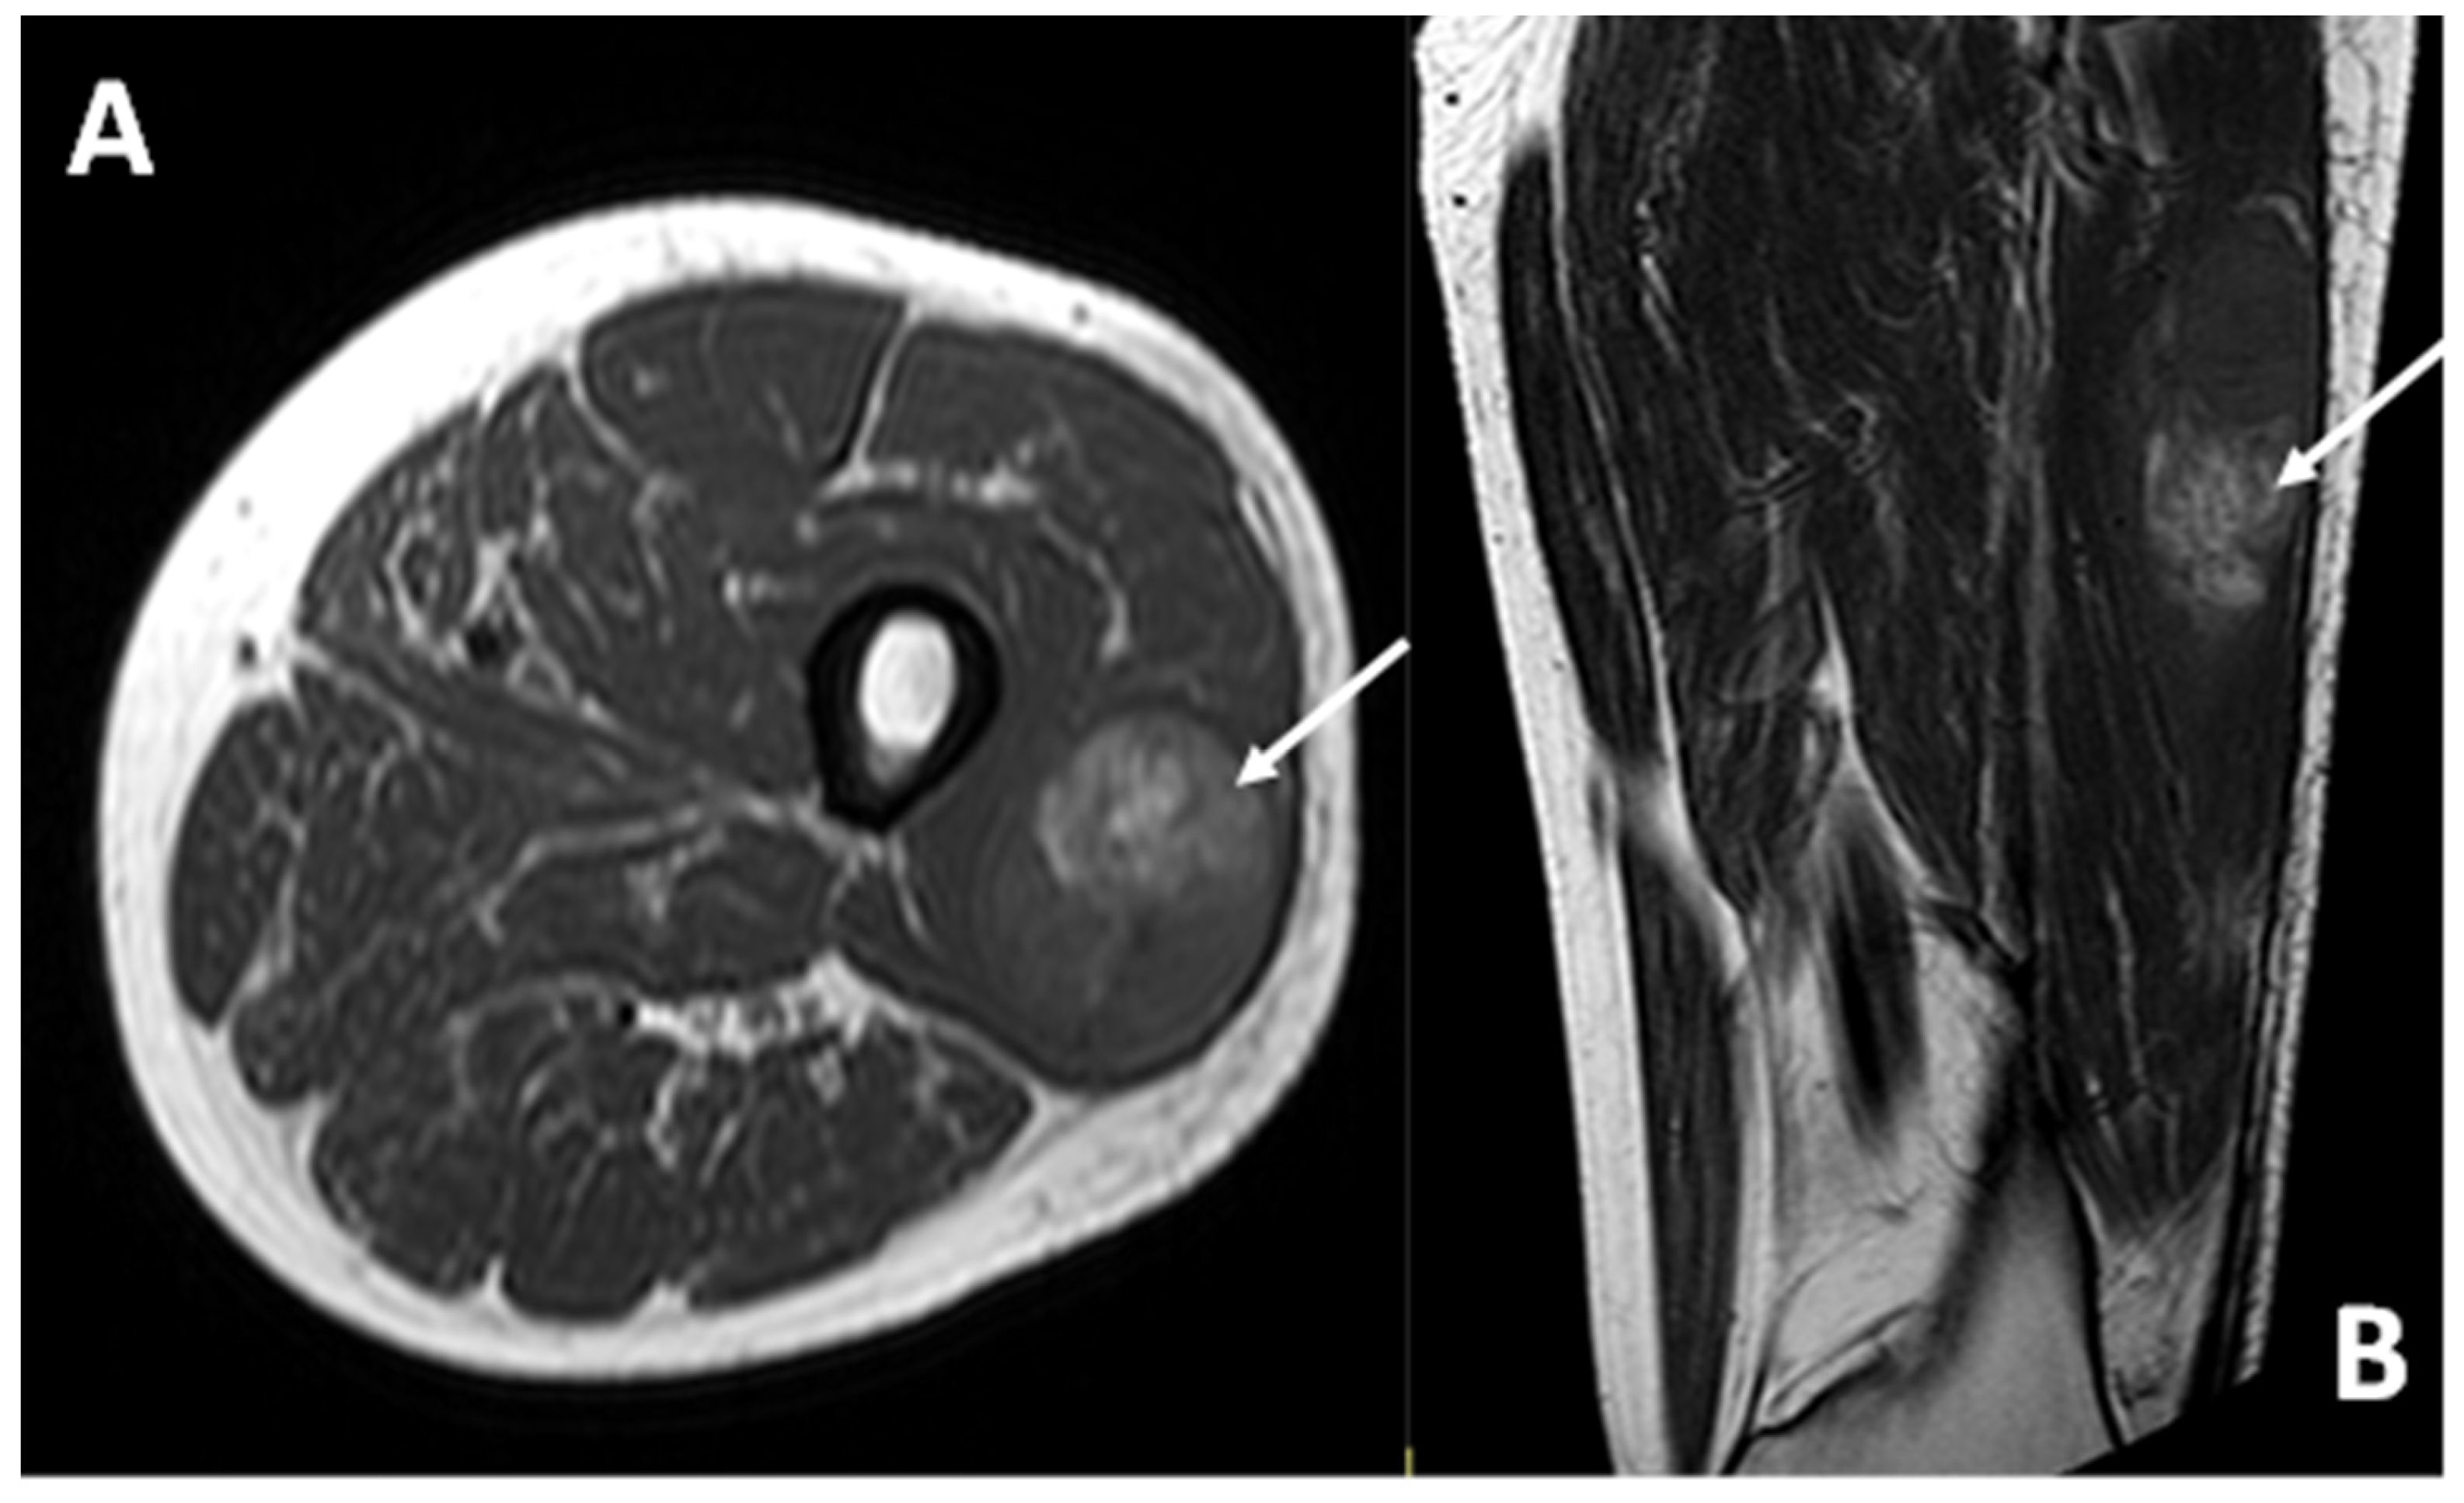

3.3.1. Dimensional Assessment (Longest Diameter—LD)

3.4.1. General MRI Features

3.4.3. Other MRI Features